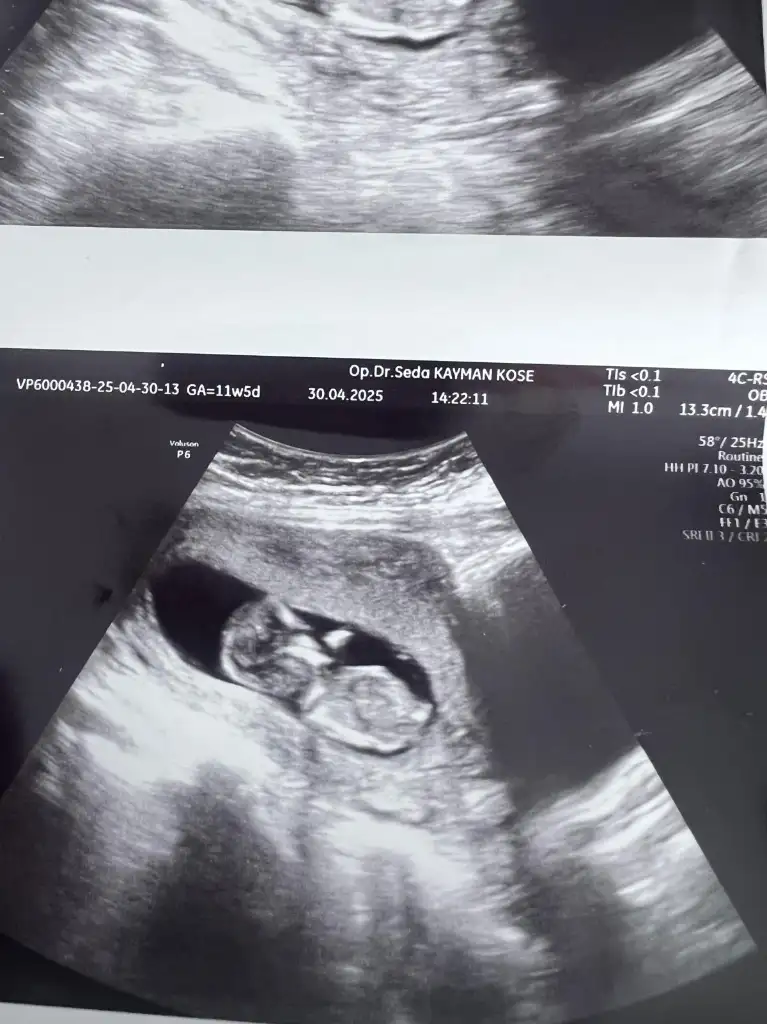

Banada bakar mısınız 12 haftalık

• 772a7cb7-dd46-4148-b878-492734ef6f59.webp

39,1 KB · Görüntüleme: 50

• 0ae49c84-b353-4504-ba74-de5b3a1e9d6a.webp

48,1 KB · Görüntüleme: 51